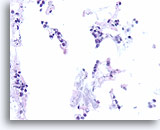

Invasief lobulair carcinoom, Borst FNA, Celblok.

Dunne strengen met lobulaire carcinoomcellen infiltreren het vetweefsel.

40X

Invasief lobulair carcinoom, Borst FNA, Celblok.

Dunne strengen met lobulaire carcinoomcellen infiltreren het vetweefsel.

40X